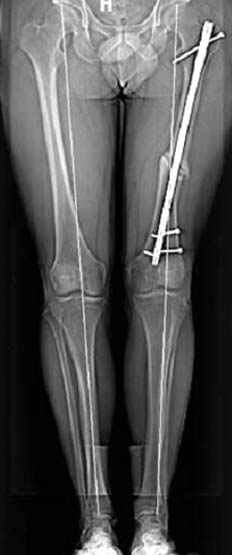

но в целом не вижу ничего ненормального в выполнении фигурных остеотомий - одномоментная коррекция оси, полная мобильность суставов, да и разрезы 4-8 см - что тоже не преступление перед человечеством. Может быть, я бы стал сторонником поперечных остеотомий ипостепенной коррекции в аппаратах, ежели бы прошел через курганскую школу, но в силу обстоятельств столкнулся с другим подходом к коррекции деформаций, который вполне эффективен и надежен, у меня не сложилось разочарования в этой технике. Поэтому и представленный раннее случай деформации бедра я бы решил сегментарной остеотомией бедра и фиксацией запирающим гвоздем - своего рода эндопротезом проксимального бедра и для больной, мне кажется, более комфортно иметь фиксацию штифтом

Несколько снимков из моей коллекции, чтобы разьяснить, почему мы до сих пор делаем различные варианты остеотомии.

На рисунке N1 предоперационный план лечения ложного сустава шейки бедра- линия ложного сустава, угол и направление введения импланта, клиновидная остеотомия в градусах и миллиметрах, второй снимок после коррекции, расчет, на сколько удлиняется конечность и размеры импланта;

N3 рисунок окончательный снимок, после операции моя рентгенограмма должен выглядеть примерно как эта картина. На N4 снимке клин перед удалением; N5 послеоперации 3 нед.; N6 окончательная рентгенограмма.

Djoldas Kuldjanov 23 Ноябрь 2004, 18:21

пластическая модель; и коррекция бедра аппаратом Илизарова.

хотя даже если бы и инфекция , то nail exchange с рассверливанием канала - вариант дебрайдмента) Я думаю, что последовательность развития событий:

Узкий к-м канал - тонкий гвоздь- усталостный перелом дистальных винтов - развитие нестабильности и как ее результат остеолиз вокруг гвоздя - деформация анатомической оси бедра. Похоже, что я понял почему аппарат, а не новый гвоздь:-)